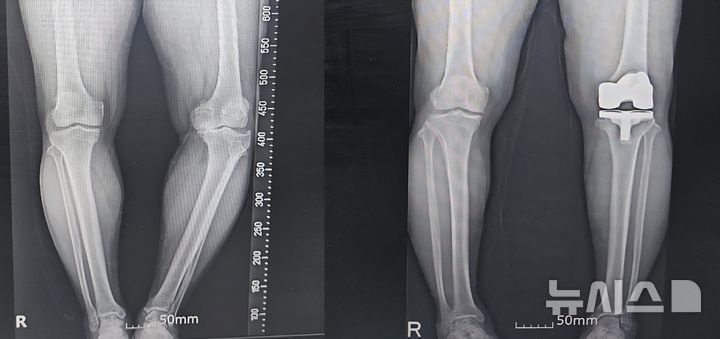

[서울=뉴시스] 퇴행성관절염과 내측변형으로 무릎이 틀어진 상태. AI와 3D모델링을 이용한 수술 전(좌)과 후(우)의 모습. (사진= 연세사랑병원 제공)

통상 15도이상 변형된 무릎은 수술과정이 복잡하고, 또 하더라도 정확하게 교정하기가 어려운 까다로운 수술로 꼽힌다. 아주 작은 오차가 있거나 정확도가 떨어지면 재수술을 해야하기 때문에 정확한 절삭면을 파악하는 것이 중요하다. 의료진이 환자의 무릎 MRI(자기공명영상)를 AI(인공지능)로 분석하자 정확한 절삭면을 알려줬다. 그는 AI·3D 맞춤형 인공관절 수술 수술로 무릎이 정확하게 교정됐고 골반도 균형이 잡혔다.